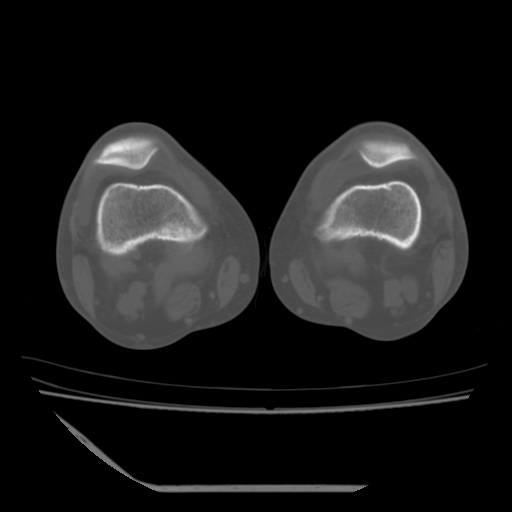

标题: CT13225:老年男性,左膝关节疼痛数月;请各位老师讨论。 [打印本页]

标题: CT13225:老年男性,左膝关节疼痛数月;请各位老师讨论。

骨质增生,骨性关节面硬化,关节积液,考虑退行性骨关节病

关节腔内少量积液,关节面退变。

双膝退变

骨质增生,骨性关节面硬化,关节间隙失常,关节积液,考虑退行性骨关节病.

骨质增生,骨性关节面硬化,关节积液,考虑退行性骨关节病。

这个病例诊断:退行性骨关节炎